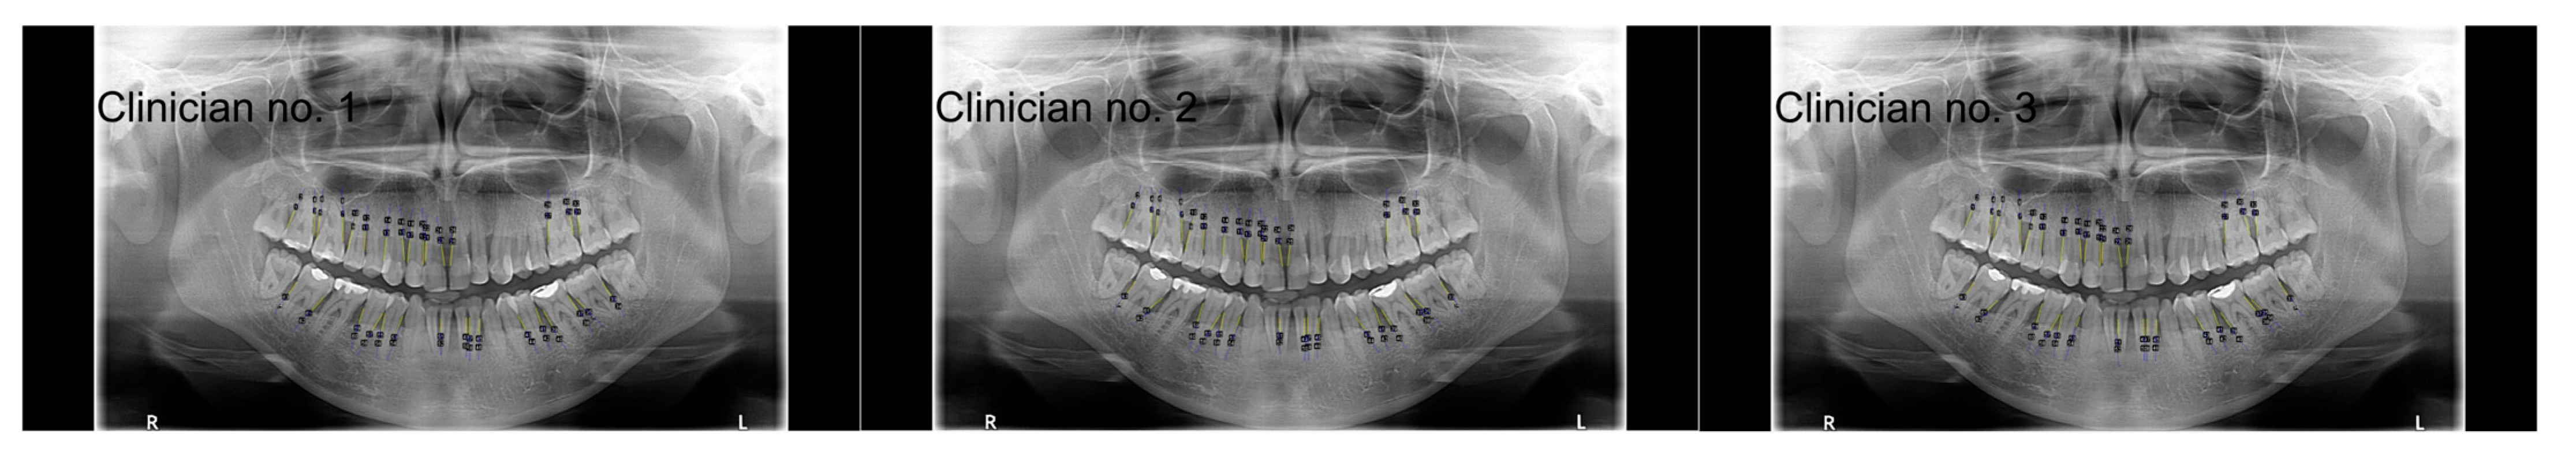

2.4.1. Analysis Conducted by Clinicians

- Three dentists participated in the research, while other studies involved a greater number of clinicians, including radiologists.

- The clinicians’ measurements of the RBH presented excellent consistency, which provided a reliable reference for comparison with the ChatGPT performance.